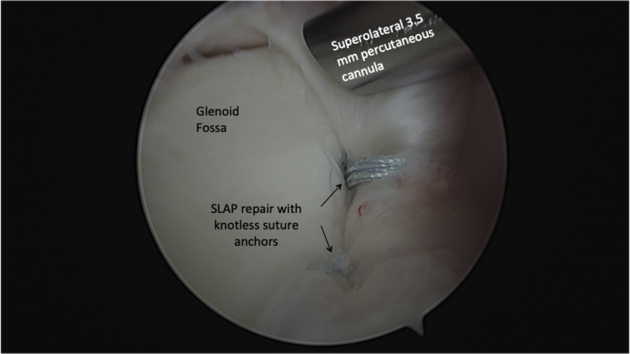

With use of the anterior portal, a 45° curve right ReelPass SutureLasso is used to place a racking hitch suture with FiberWire in the 1 o’clock position. At this point, a superolateral 5.4-mm percutaneous cannula is placed anterior and lateral to the acromion to facilitate optimal anchor placement. With a Percutaneous Insertion Kit (Arthrex), a spinal needle is inserted posterior to the biceps tendon under direct visualization through the posterior portal. A nitinol wire is placed through the needle, and the needle is removed. A dilator is placed over the nitinol wire, and then the wire is removed. The final step is to place the cannula over the dilator and remove the dilator. A drill guide is then placed through the percutaneous cannula, a pilot hole is drilled, and a 2.9-mm PushLock is impacted. Once the 1 o’clock PushLock anchor is secured, a 2 o’clock anchor is placed using the same technique and portals (Figs 5 and 6).

Fig 5.

Arthroscopic image of the left glenohumeral joint viewing from the posterior portal with the patient in a right modified lateral decubitus position. The superior labrum has been repaired posterior to the biceps tendon with knotless suture anchors in the 1 o’clock and 2 o’clock positions.

Fig 6.

Arthroscopic image of the left glenohumeral viewing from the posterior portal with the patient in a right modified lateral decubitus position. The anterior labral repair is visualized with knotless suture anchors at 10 o’clock and 8 o’clock. The SLAP repair is visualized with knotless suture anchors at 1 o’clock and 2 o’clock. Note the labrum is anatomically reduced at each point of fixation.